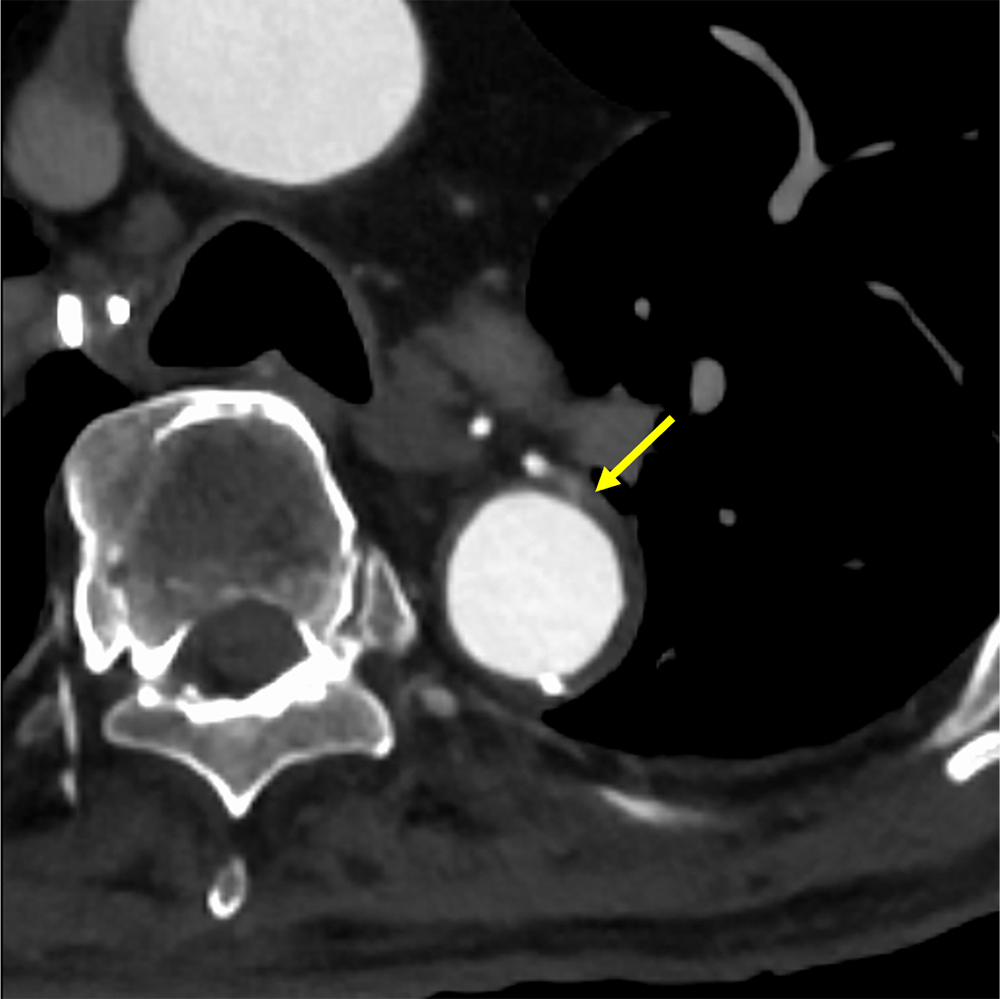

症例は左膿胸に対し術後の既往がある患者。少量の喀血が継続することを主訴に呼吸器内科を受診し、造影CTが施行された。左肺下葉にはすりガラス陰影とconsolidationがみられ、喀血の吸い込み像と思われた。左気管支動脈は拡張していたが、起始部で高度狭窄が疑われた。BAE施行目的に当院放射線科に紹介された。

当該疾患の診断における造影CTの役割

今回は臨床的に左気管支動脈が原因として疑われていたが、起始部が極めて細径であった。カテーテル治療が困難と思われたが術前造影CTを施行し、thin sliceにて起始部のレベル・分岐方向を同定することができた。このことで必要十分な塞栓術が施行され、治療を完遂することができた症例である。

また本症例では未掲載だが、肺動脈相を撮像することで、肺動脈瘤の有無に関しての評価も行なっている。